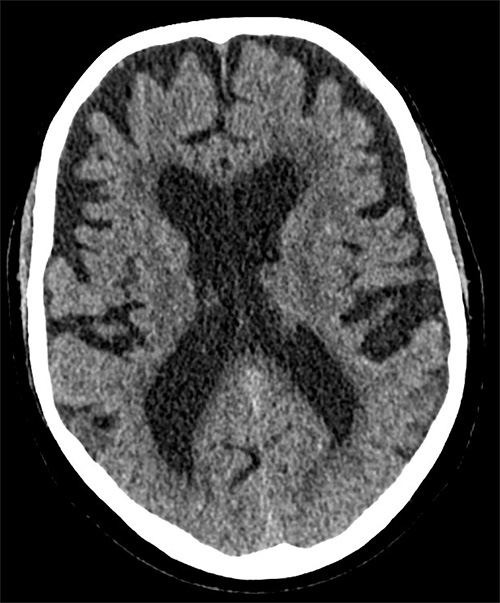

Ventrikulomegali tillsammans med ett högt Evans-­index ses dock inte enbart vid hydrocefalus utan även vid hjärnatrofi.

DT-bild som visar generell hjärnatrofi där ventriklarna vidgats på grund av nedbrytning av parenkym.